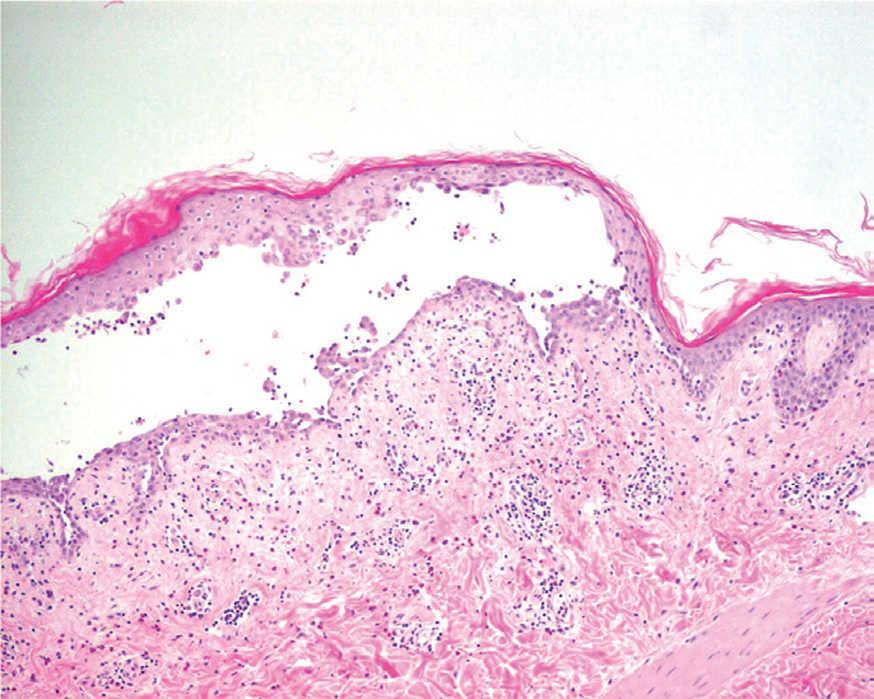

El PF y el eritematoso pueden mostrar un patrón de espongiosis eosinofílica, una ampolla subcórnea con escasos queratinocitos acantolíticos que evolucionan a queratinocitos granulares disqueratósicos característicos de esta enfermedad (fig. 21). El infiltrado inflamatorio observado es variable, dependiendo de la antigüedad de la lesión, el tipo de lesión biopsiada y de la existencia de impetiginización 128.

Fig. 21.--Ampolla intraepidérmica superficial en pénfigo foliáceo.